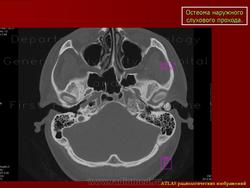

Остеома.

Приложения:

1.os_.slayd343.jpg2.os_.slayd344.jpg3.os_.slayd345.jpg